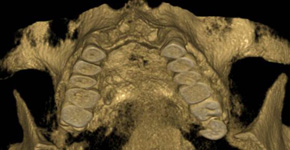

3D DVT - NewTom

Je speciální zubní digitální tříprostorový tomograf (3D), který umožňuje na základě jediného

snímkování vytvořit všechny typy RTG zobrazení, které jsou pro lékaře potřebné. Díky používané technologii tzv. „kuželového paprsku“ a speciálním senzorům je

výrazně zmenšená dávka záření - o více jak 80% proti klasickému CT vyšetření. To je významné zejména u dětí. Pomocí tohoto přístroje je možné zjisti skutečnou situaci v čelistních kostech pacienta tedy množství kosti - můžeme změřit skutečnou šířku i výšku kosti, i kvalitu kosti (hustotu) v místě uvažované implantace. 3D (tříprostorové) zobrazení umožňuje zvýšit prostorovou představu operatéra ještě před vlastní operací a zároveň pacientovi lépe objasnit a ukázat oblast plánovaného zavedení implantátu.

Pacient „neumí číst“ RTG snímky, ale díky 3D zobrazení vidí „svoji skutečnou čelist“

- např. jak je nízká či úzká, vidí průběh nervu nebo velikost čelistní dutiny, což mu umožní i pochopení nutnosti v některých případech provést pomocné zákroky ještě před vlastním zavedením implantátu (viz. kostní štěp, sinus lift, kostní granulát...).

Vyšetření pomocí tohoto přístroje používáme i ve stomatochirurgii (zlomeniny čelistí, zuby moudrosti, cysty, onemocnění čelistního kloubu), ortodoncii (retinované zuby, nadpočetné zuby), parodontologii atd.

NewTom Giano

Jedná se o nejnovějším přístroj ze skupiny dentálních hybridních CBCT (3D) + 2D (pan i ceph) systémů. Opět umožňuje na základě jediného snímkování vytvořit všechny typy RTG zobrazení, které jsou pro lékaře potřebné. Používaná technologii tzv. „kuželového paprsku“ a speciální senzory pro minimální zátěž při snímkování pacienta.

Vyšetření pomocí tohoto přístroje (nebo

3D DVT - NewTom) a získaná data používáme

pro každou implantaci, dále ve stomatochirurgii (zlomeniny čelistí, zuby moudrosti, cysty, onemocnění čelistního kloubu), ortodoncii (retinované zuby, nadpočetné zuby), parodontologii atd.